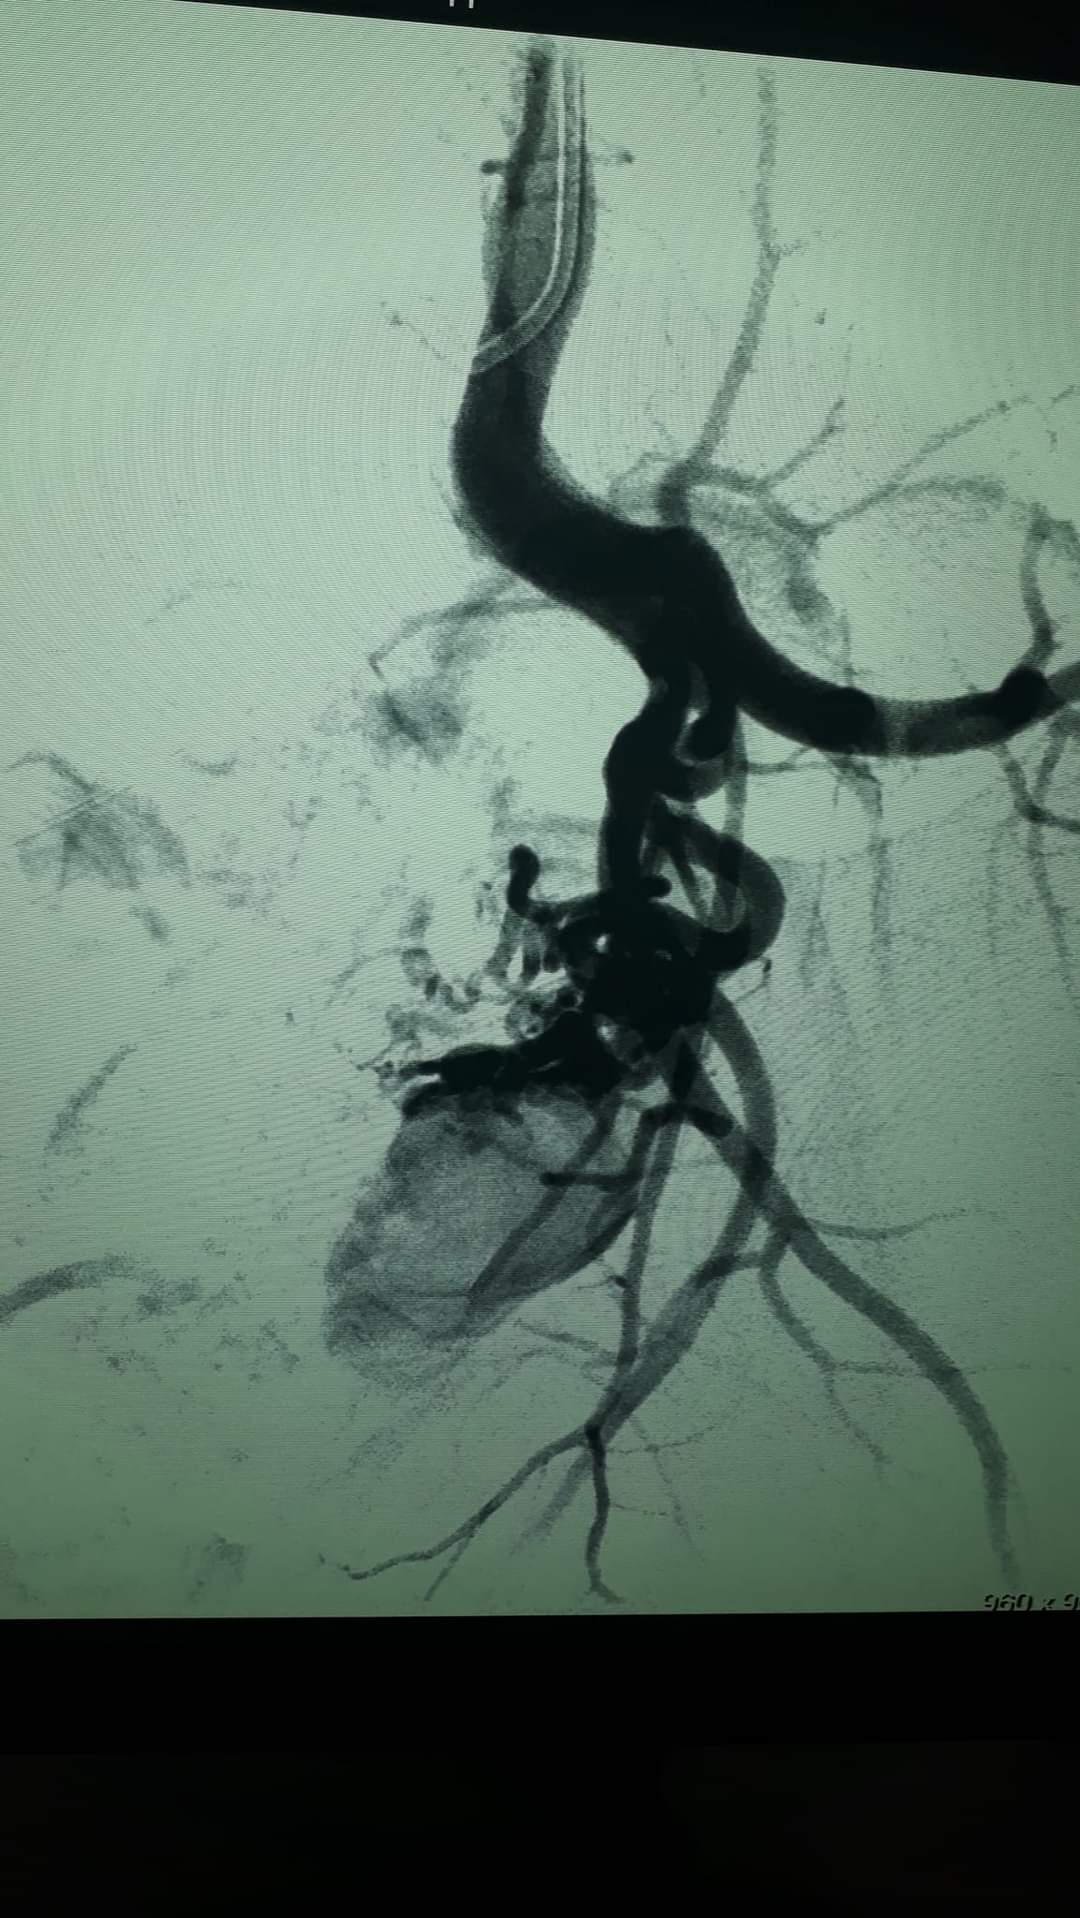

تمكن طاقم طبي فلسطيني من قطاع غزة من انقاذ حياة شاب في العشرين من عمره، بعد إجراء عملية جراحية، وُصفت "بالنادرة".

حيث تم إغلاق إنتفاخ في أحد الشرايين المتفرعة من "الشريان الحرقفي العميق" في الحوض. حيث كان يتسبب في ألام شديدة لمريض في الثانية والعشرين من عمره.

وقال الدكتور محمد كلوب استشاري اول جراحة الأوعية الدموية والقسطرة الطرفية، أن حياة المريض كانت محفوفة بالخطر الشديد، نتيجة الوصلات الشريانية والوريدية التي كانت معرضة للإنفجار وتهدد حياة المريض.

واعتبر الدكتور كلوب في تصريح صحفي أن هذه من الحالات النادرة جداً، وقد أُجريت هذه العملية، برئاسة دكتور محمد مطر.